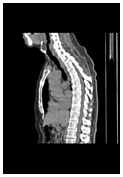

身体の形態ははっきり

見えているが病変が不明

PET-CT検査は、がん細胞の成長・増殖・転移や治療効果を知るための有効で的確な検査法です。病巣の有無を調べるためPET(陽電子放出断層撮影)と、病巣場所を確認するためのCT(コンピュータ断層撮影)による2つの画像を同時に撮影することで、がんの有無と位置・転移場所・大きさを、一回の全身撮影で診断できます。